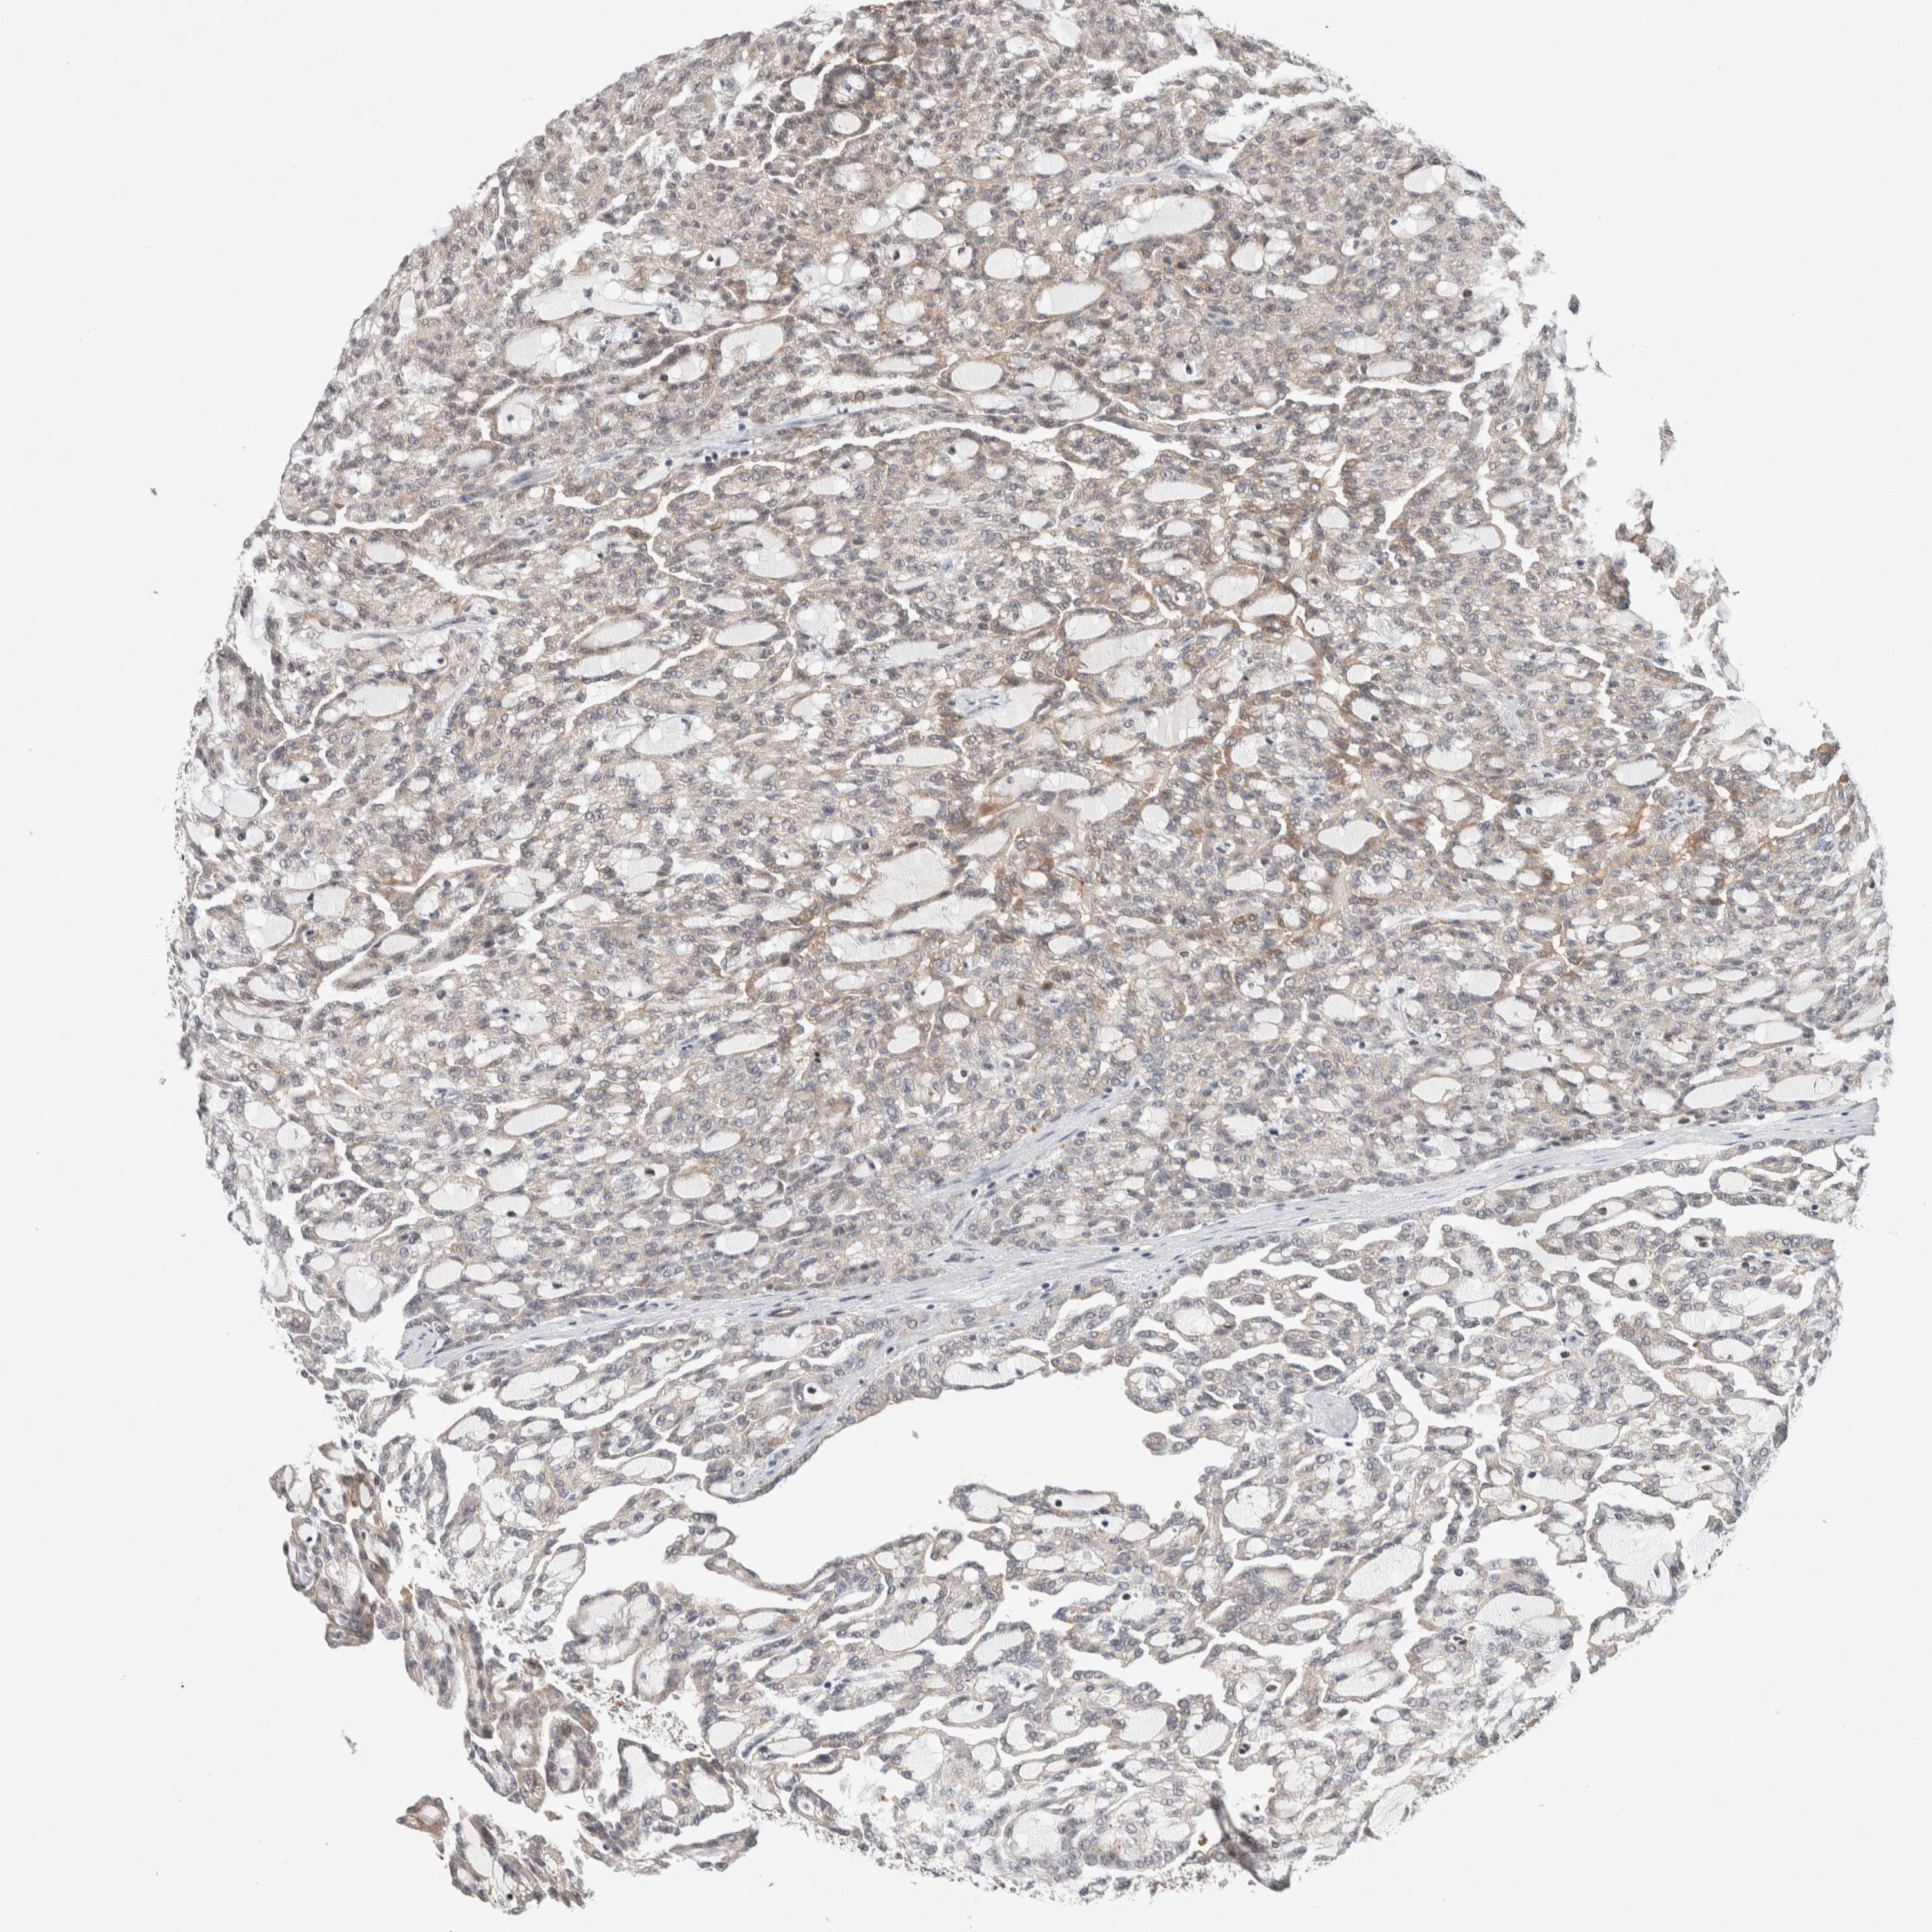

KIDNEY RENAL PAPILLARY CELL CARCINOMA (TCGA) - Interactive survival scatter ploti

The Survival Scatter plot shows the clinical status (i.e. dead or alive) for all individuals in the patient cohort, based on the same data that underlies the corresponding Kaplan-Meier plots. Patients that are alive at last time for follow-up are shown in blue and patients who have died during the study are shown in red.

The x-axis shows the expression levels (FPKM) of the investigated gene in the tumor tissue at the time of diagnosis. The y-axis shows the follow-up time after diagnosis (years). Both axes are complimented with kernel density curves demonstrating the data density over the axes. The top density plot shows the expression levels (FPKM) distribution among dead (red) and alive patients (blue). The right density plot shows the data density of the survived years of dead patients with high and low expression levels respectively, stratified using the cutoff indicated by the vertical dashed line through the Survival Scatter plot. This cutoff is automatically defined based on the FPKM cutoff that minimizes the p-score. The cutoff can be changed by dragging the vertical line or by entering a cutoff value in the square labeled "Current cut-off".

Under the Survival Scatter plot the p-score landscape (black curve; left axis) is shown together with dead median separation (red curve; right axis). Dead median separation is the difference in median mRNA expression between patients who have died with high and low expression, respectively. It is calculated as follows: median FPKM expression of dead patients with high expression - median FPKM expression of dead patients with low expression. This is intended to aid the user in visually exploring custom cutoffs and the associated p-scores and dead median separation.

Individual patient data is displayed and can be filtered by clicking on one or more of the category buttons on the top of the page. Categories describing expression level and patient information include: high, low, alive, dead, female, male and tumor stages. The scale of the x-axis can be toggled between linear and log-scale by clicking on the "x log" button. Mouse-over function shows TCGA ID, patient information and mRNA expression (FPKM) for each patient.

& Survival analysisi

Kaplan-Meier plots summarize results from analysis of correlation between mRNA expression level and patient survival. Patients were divided based on level of expression into one of the two groups "low" (under cut off) or "high" (over cut off). X-axis shows time for survival (years) and y-axis shows the probability of survival, where 1.0 corresponds to 100 percent.

KCNK1 is potential prognostic, high expression is unfavorable in Kidney Renal Papillary Cell Carcinoma (TCGA)